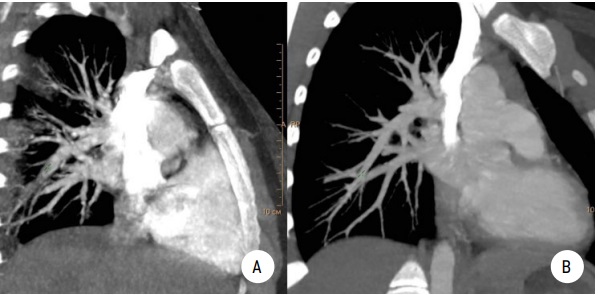

69-76 90

Аннотация

Актуальность. Тромбоэмболия легочной артерии (ТЭЛА) характеризуется острой перестройкой параметров центральной гемодинамики в большом и малом кругах кровообращения и является одним из частых жизнеугрожающих состояний среди взрослых пациентов. Несмотря на то что первое описание ТЭЛА было представлено фон Лешнером в 1861 году, до настоящего времени в педиатрической практике нет должной настороженности к подобному осложнению. Это объясняется не только отсутствием системных знаний о распространенности ТЭЛА в детской популяции, но и из-за стертости, а порой и нетипичной, в отличие от взрослого пациента, клинической картины. Неверная интерпретация имеющихся симптомов, ошибочная трактовка данных инструментальных методов исследования неизбежно приводят к неверному диагнозу: пневмония, сердечная недостаточность, дебют онкологического заболевания, что объясняет высокую летальность при ТЭЛА у детей.

Цель. Демонстрация случаев ТЭЛА при наличии значимых факторов риска — прием пероральных контрацептивов, снижение уровня протеинов C и S у двух девочек-подростков.

Материалы и методы. Представлены 2 случая клинически и/или инструментально подтвержденных эпизодов ТЭЛА у девушек 17 и 14 лет. ИМТ в одном и другом случае составил 25,9 и 25,15 кг/м2 соответственно. Среди инструментальных методов исследования были выполнены ЭКГ, трансторакальная ЭхоКГ, мультиспиральная компьютерная томография (МСКТ) с контрастированием. Лабораторная диагностика антифосфолипидного синдрома, анализ на тромбофилию были обязательным дополнением клиническому, биохимическому анализам крови и коагулограмме с определением уровня АТ-III и D-димера.

Результаты. Среди клинических симптомов, имеющих диагностическую ценность в дебюте заболевания, были одышка, боли в области грудной клетки, кашель, кровохарканье. Ни в одном, ни в другом случае эпизод ТЭЛА не привел к повышению давления в легочной артерии, о чем свидетельствовали показатели давления в правом желудочке (ПЖ): 24 и 20 мм рт. ст. соответственно. МСКТ с контрастированием подтвердила диагноз субмассивной ТЭЛА и признаки инфаркт-пневмонии в одном и другом случаях. УЗДГ не обнаружила источника ТЭЛА в сосудах нижних конечностей и малого таза ни у одной из девушек. Прием пероральных контрацептивов в одном случае и снижение уровня протеинов С и S в другом явились значимыми факторами развития ТЭЛА. Лечебная тактика заключалась в назначении низкомолекулярных гепаринов (НМГ) с переходом на непрямые антикоагулянты: апиксабан и варфарин соответственно. Выполненная через месяц МСКТ свидетельствовала о положительной динамике заболевания, но не полном восстановлении воздушности легочной ткани. Терапия непрямыми антикоагулянтами была продолжена.

Заключение. Частота встречаемости ТЭЛА в детской популяции реже, чем у взрослых, но это не снижает уровня значимости данного грозного осложнения в педиатрической практике. Центральные венозные катетеры, септические осложнения, длительная иммобилизация, шунтированная гидроцефалия, онкология, ожирение являются наиболее вероятными причинами ТЭЛА у детей, как и у взрослых пациентов. Прием оральных контрацептивов и наследственные тромбофилии в двух наших наблюдениях свидетельствуют о других не менее очевидных причинах возникновения ТЭЛА у детей подросткового возраста.